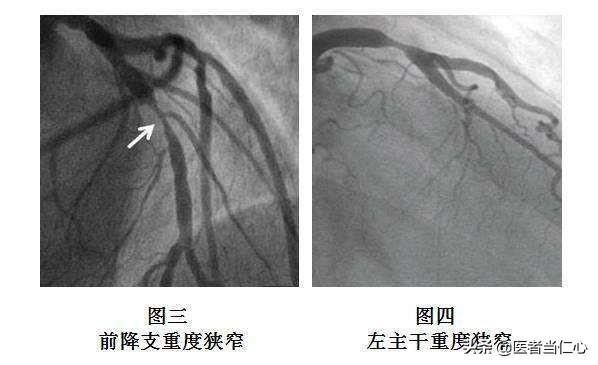

①明確な診断冠動脈性心疾患の診断は、現在の医療レベルでは、次のような方法で難しいことではない。冠動脈造影冠動脈疾患の確定診断ができる。冠動脈に直接カテーテルを通し、造影剤を出して冠動脈を画像化することで、閉塞の場所や程度が明確になり、その後の治療の根拠となります。これが冠動脈疾患の最も一般的な治療法である理由です。冠動脈疾患診断の "ゴールドスタンダード"。。

冠動脈疾患とは、心臓に血液を供給する血管である冠動脈に病変が生じ、心臓への血液供給量と酸素消費量のバランスが崩れ、心筋虚血や低酸素症が生じる心臓病である。冠動脈疾患の一般的な病態生理学的基盤は冠動脈アテローム性動脈硬化症である。 冠動脈疾患は、冠動脈の狭窄が50%を超えるか、心筋虚血の証拠がある場合に診断される。

狭心症の症状、トロポニンの上昇、心電図の変化などは冠動脈疾患のスクリーニングに有用であるが、冠動脈疾患の診断のゴールドスタンダードは冠動脈造影検査である。冠動脈造影検査は侵襲的な手技であるが、冠動脈疾患の診断と重症度の把握にかけがえのない役割を担っている。冠動脈造影検査は造影剤を注入することによって、冠動脈の狭窄の程度をはっきりと観察することができ、冠動脈の狭窄が50%に達すると冠動脈性心臓病と診断することができます。 冠動脈造影検査は同時に冠動脈の病変部分と量を把握することができ、病態を評価するための非常に貴重な手がかりを提供することができます。冠動脈疾患は治るのか?現在の医療技術では、冠動脈疾患を治すことはできません。しかし、アスピリンやクロピドグレルなどの抗血小板凝集薬、スタチンなどのプラーク安定化薬、ベタブロッカーやプリリジーなどの予後改善薬などの合理的な治療により、心筋梗塞に移行するリスクを減らすことは可能です。冠状動脈性心臓病

まとめると、狭心症、トロポニンの上昇、心筋虚血を示唆する心電図は冠動脈疾患のスクリーニングに有用である。 しかし、冠動脈疾患の診断のゴールドスタンダードは冠動脈造影であり、50%までの冠動脈狭窄が冠動脈疾患の診断となり、同時に冠動脈病変の位置と数を把握することができる。冠動脈疾患は治すことはできないが、妥当な治療によって冠動脈疾患の進行を遅らせ、心筋梗塞のリスクを減らすことができる。